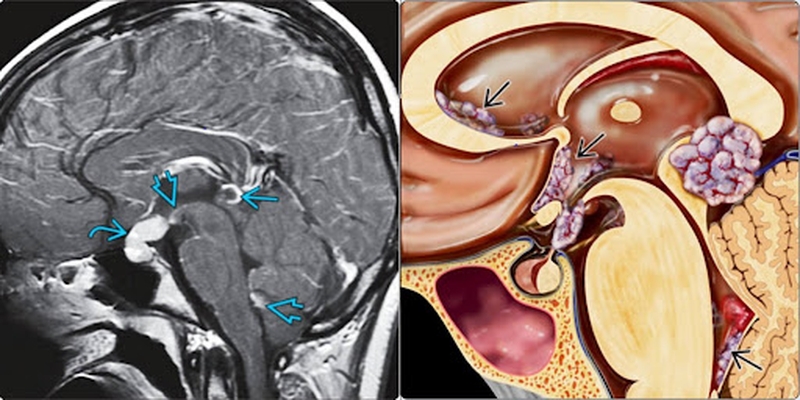

U tế bào mầm ở trẻ em: giới thiệu1 U tế bào mầm nội sọ

U tế bào mầm ở trẻ em: giới thiệu2 Khối u ở vùng tuyến yên gây rối loạn thị giác và khứu giác

• Những khối u tế bào mầm nằm ở vùng tuyến yên là những tế bào mầm di chuyển và phát triển thành khối u ở vùng tuyến yên có thể gây ra một số tình trạng về rối loạn thị giác, loạn thị và rối loạn khứu giác ở trẻ em.